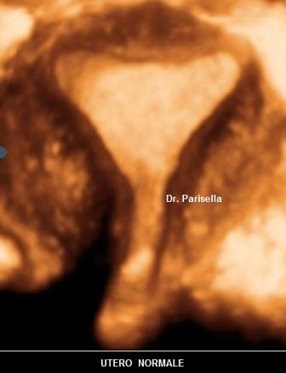

Utero Setto

E' la malformazione uterina più frequente (55% delle anomalie mulleriane); è la conseguenza di un incompleto riassorbimento del setto uterovaginale dopo la fusione dei dotti di Muller.

Ecograficamente è fondamentale la visualizzazione del profilo del fondo uterino per differenziarlo dall'utero bicorne. Nell'utero setto il profilo del fondo può essere convesso, appianato o a volte concavo. L'eco 3D, permettendo una accurata scansione coronale consente, nella maggior parte dei casi, di poter differenziare questa anomalia dall'utero bicorne.

Si distinguono due tipi di utero setto:

- utero setto completo: il setto si estende dal fondo alla cervice

- utero setto incompleto: il setto origina dal fondo e non giunge all'OUI.